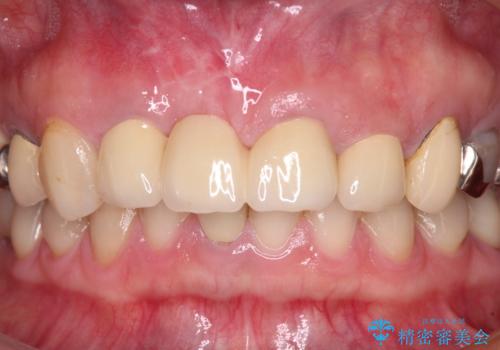

- 以前から前歯の根が折れていると言われていたものの放置しており、いよいよ痛みが気になってきたとのことで来院された患者様です。

検査の結果、右前歯の歯根が縦に破折していることが分かりました。

破折している歯は抜歯をし、歯肉が窪んでしまうので、傷口の治りを待って、歯肉移植を行うこととしました。

歯肉移植終了後、オールセラミックブリッジにて補綴することとしました。

歯肉移植により歯肉ラインや歯の形態を整えることができ、ブリッジによる補綴としたことで舞えば全体の色調を整えることができました。